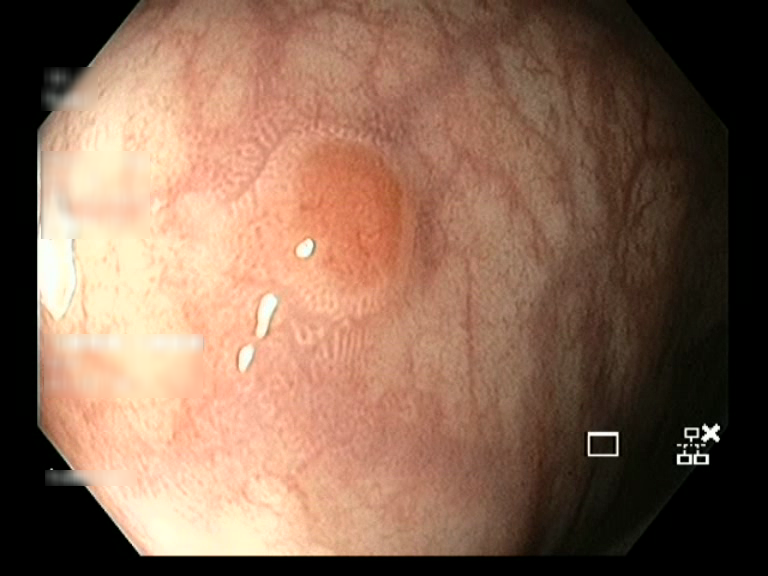

| Lesion | White Light Frame | NBI Frame | White Light Video | NBI Video | Camera Calibration |

| serrated_01 |  |

|

WL.mp4 | NBI.mp4 | cam.xml |